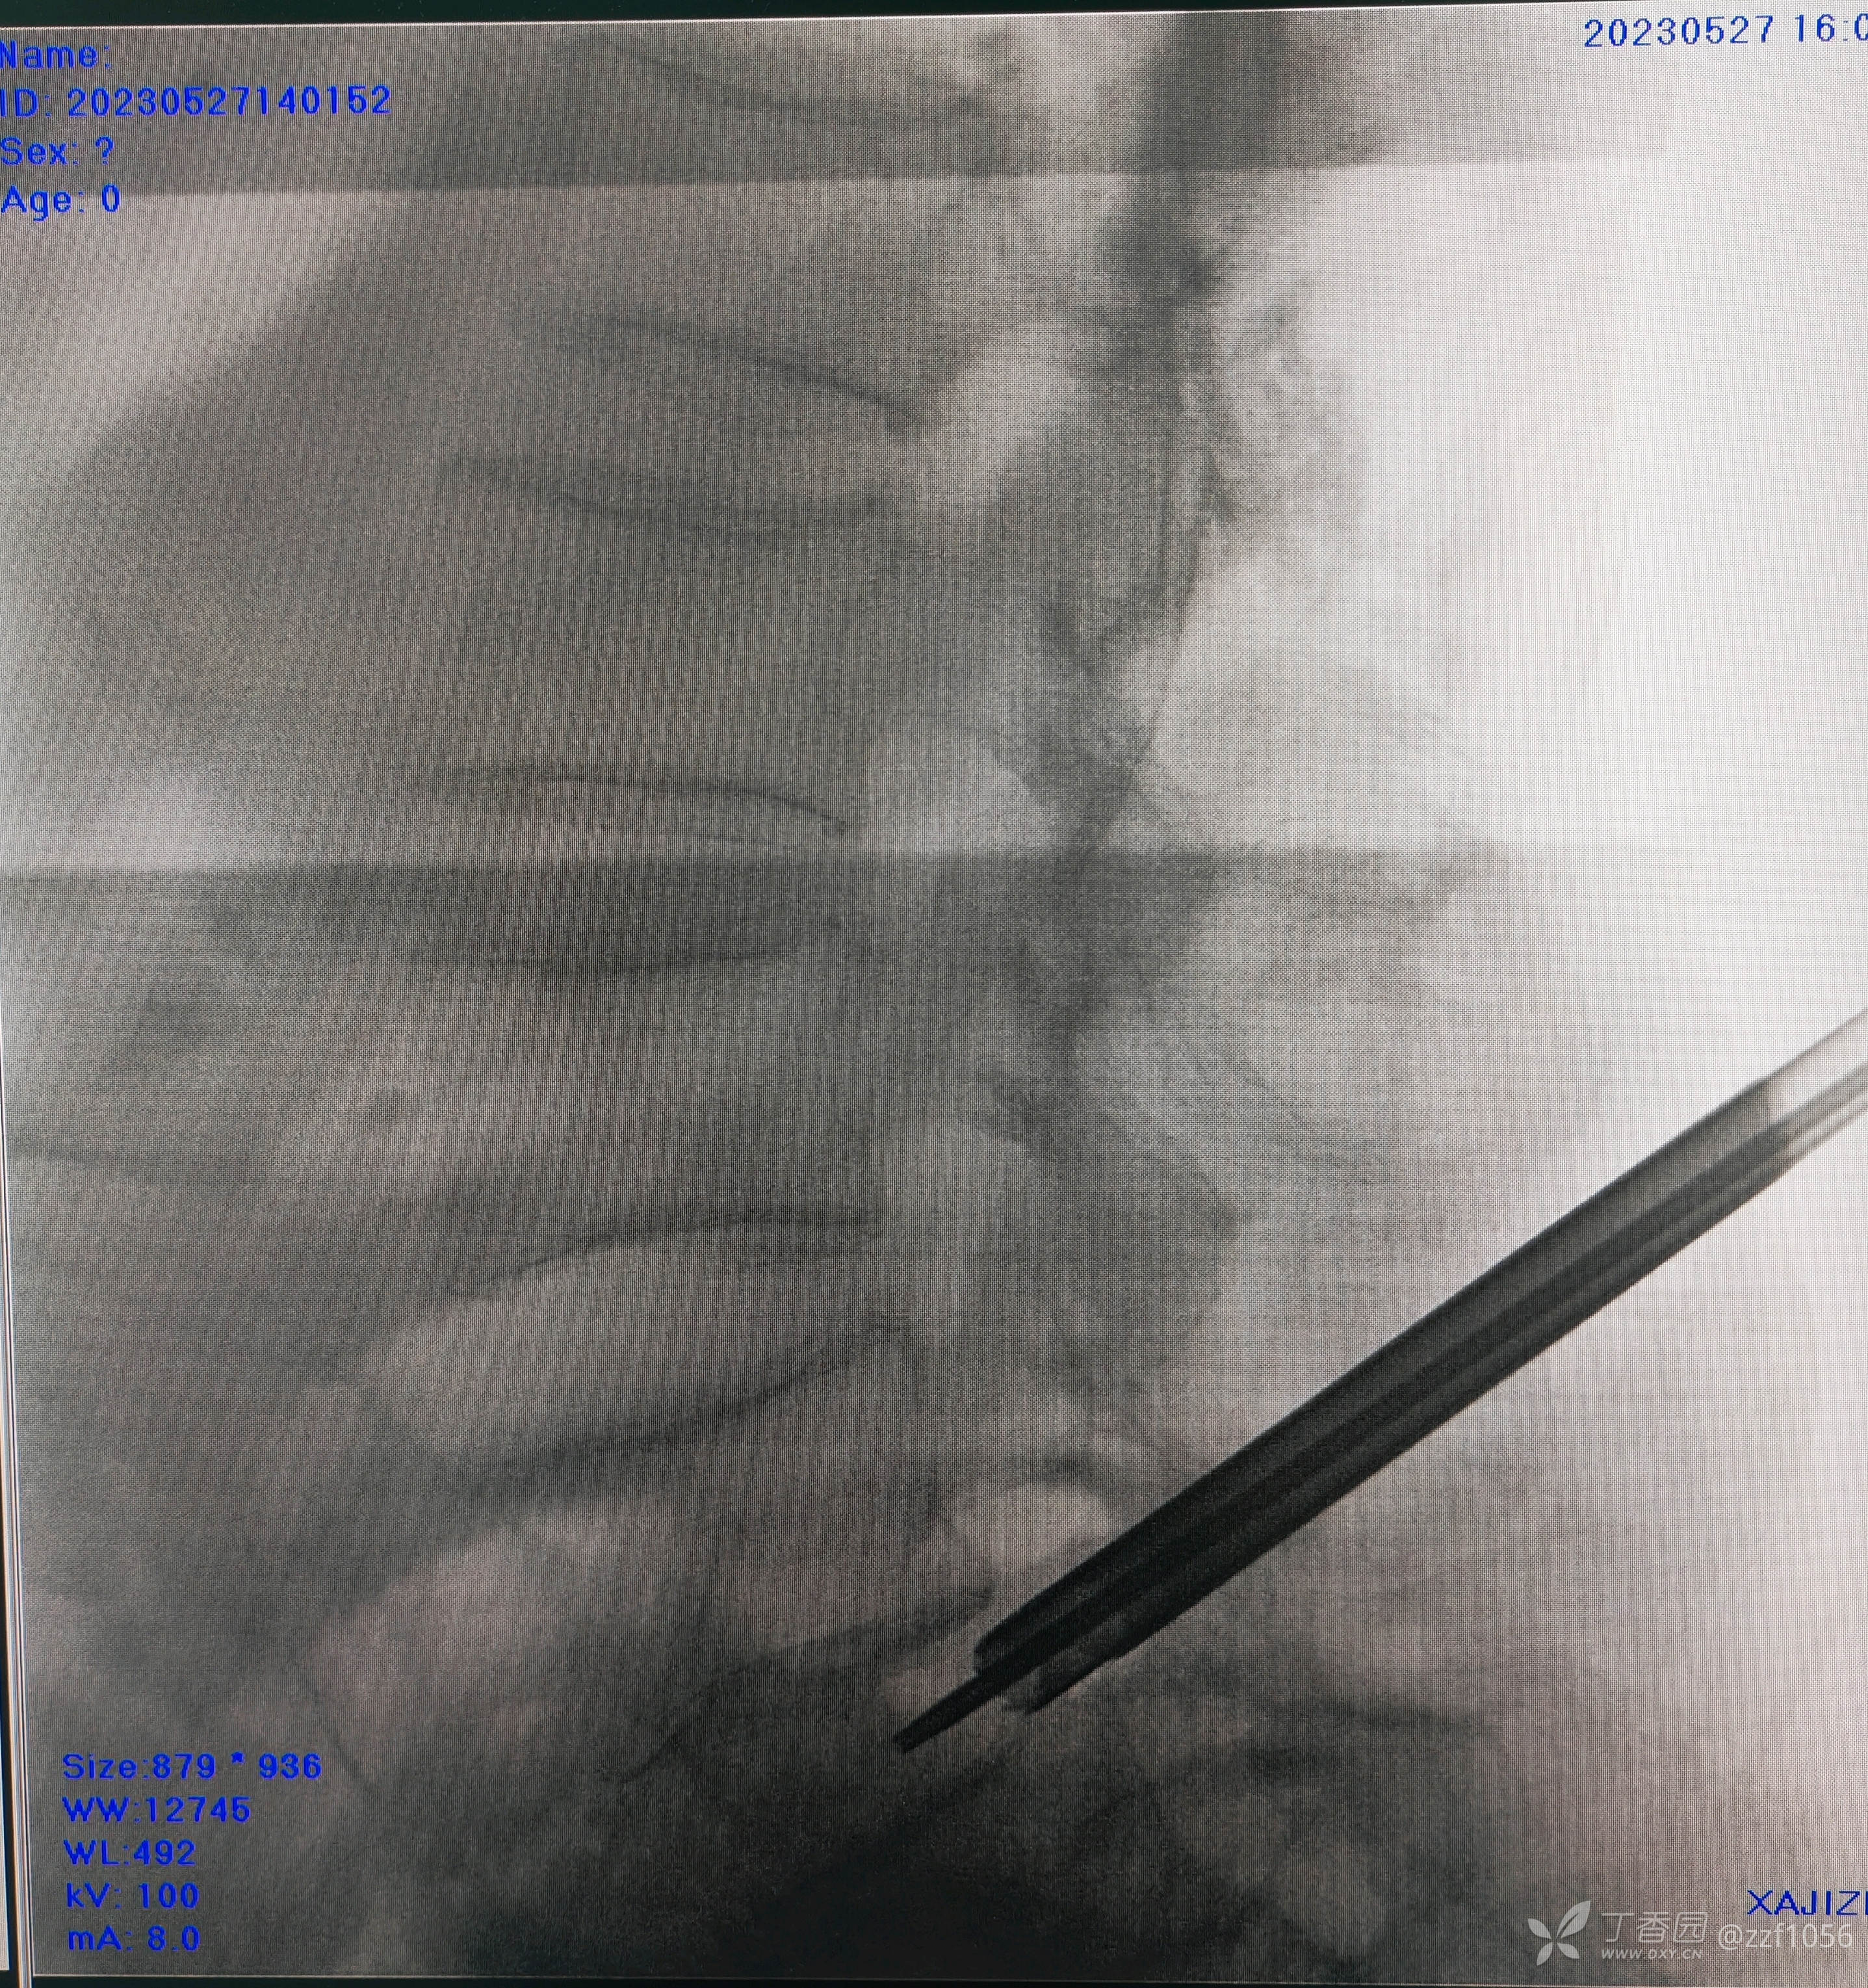

再次手术室阻滞,标准化再次阻滞L4/5,确实效果不显著,增加阻滞L5/S1后返回病房,患者诉疼痛有一定程度缓解,最少能做床边了,但仍旧疼痛,夜间睡眠无疼痛发作